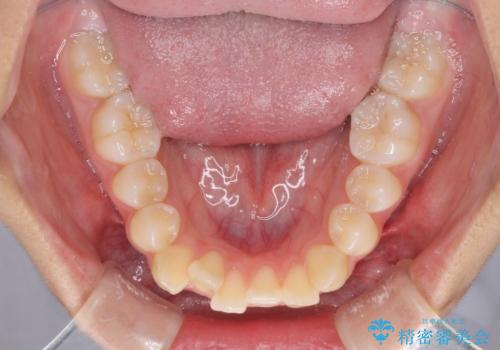

- 前歯のデコボコと八重歯を気にして来院された患者様です。

本人はあまり実感はありませんでしたが、同席されたご家族より口がすぐに開いてしまうことを指摘されていました。

口元に力の入る歯列であったため、上顎左右第一小臼歯4本を抜歯するワイヤー矯正を行うこととしました。

当初は八重歯やデコボコが一番気になっていましたが、抜歯矯正により口元の突出感が改善されるにつれ、口の閉じやすさを実感するようになってきました。